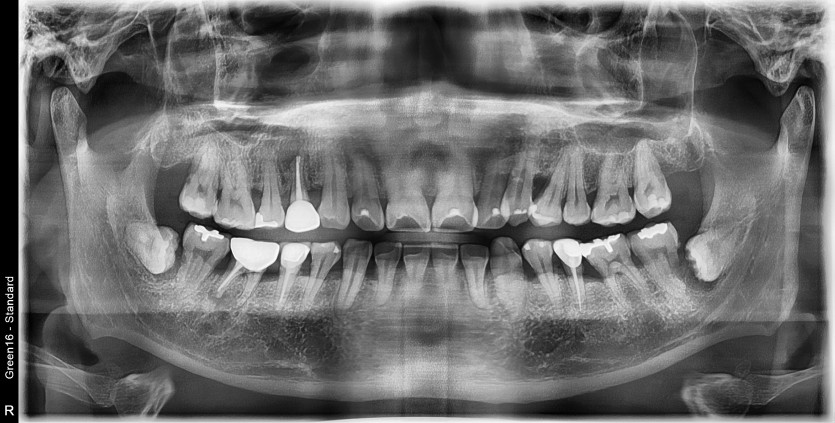

#38 사랑니 발치

구강외과 전문의가 발치했습니다.